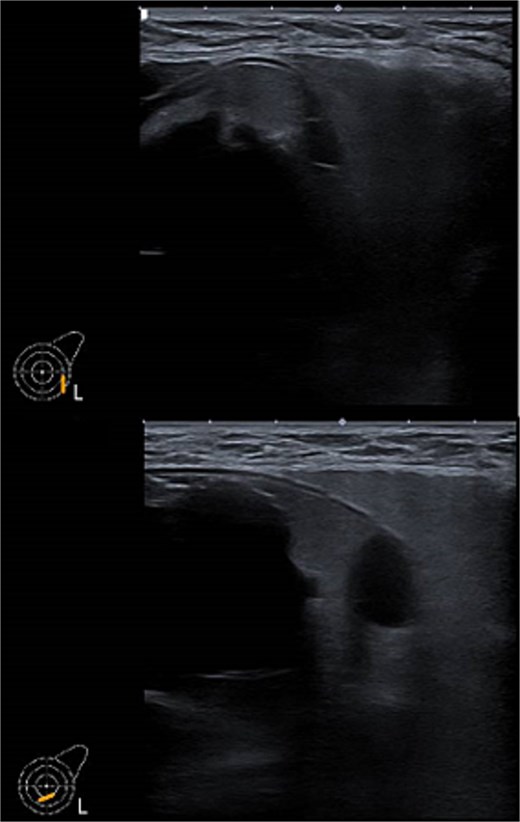

Ultrasound of left breast and axilla: Revealed rupture of the left implant with intracapsular and extracapsular leakage, along with echogenic peri-implant fluid. Enlarged axillary lymph nodes were visualized (Figs 1 and 2).

Ultrasound of the left breast showed rupture of the left breast implant with intracapsular and extracapsular leakage, surrounded by echogenic peri-implant fluid.

Ultrasound of the left axilla showed the typical appearance of the lymph node siliconoma.